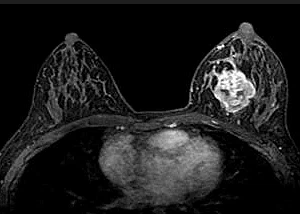

유방암은 유방조직에 악성 세포 암이 발생하는 것을 의미합니다. 유방조직이 적은 남자 또한 유방암에 걸릴 수 있습니다.

유방암은 일반적으로 남자보다 여자한테 자주 발생하고, 매해 발생률이 약간씩 늘고는 있지만 정확한 이유은 아직 확실히 알려지지 않았습니다. 생활환경이나 유전적 요인 정도로 발생한다고 알려져 있습니다.

유방암은 30대 중후반에서 60대 초기까지의 여성분들한테 가장 자주 나타나는 질환이었지만, 최근은 젊은 여성층인 20~30대에서도 유방암 유발률이 오르고 있기 때문에 여성들의 경우 특히나 주의해야 하는 질환 중 하나입니다.